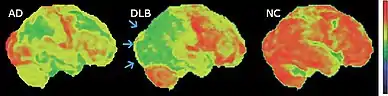

Medical imaging in AD and DLB

MRI of brain showing hippocampus atrophy (red rectangles), more prominent in AD than DLB, compared to normal control (NC)

FDG-PET horizontal cross section of brain, with brighter areas indicating higher metabolism. The cingulate island sign is indicated by the arrowhead.

FDG-PET of brain surface, with the color red indicating areas of high metabolism. The occipital lobe in DLB (arrows) shows less activity than in AD.

While 74% of people with autopsy-confirmed DLB had deficits in planning and organization, they show up in only 45% of people with AD.[147] Visuospatial processing deficits are present in most individuals with DLB,[66] and they show up earlier and are more pronounced than in AD.[148] Hallucinations typically occur early in the course of DLB,[5] are less common in early AD, but usually occur later in AD.[85] AD pathology frequently co-occurs in DLB and is associated with more rapid decline; cerebrospinal fluid (CSF) testing may reveal an "Alzheimer's pattern" of higher tau and lower amyloid beta.[130]

PET or SPECT imaging can be used to detect reduced dopamine transporter uptake and distinguish AD from DLB.[57][149] Severe atrophy of the hippocampus is more typical of AD than DLB.[150] Before dementia develops (during the mild cognitive impairment phase), MRI scans show normal hippocampal volume. After dementia develops, MRI shows more atrophy among individuals with AD, and a slower reduction in volume over time among people with DLB than those with AD.[33] Compared to people with AD, FDG-PET brain scans in people with DLB often show a cingulate island sign.[33]